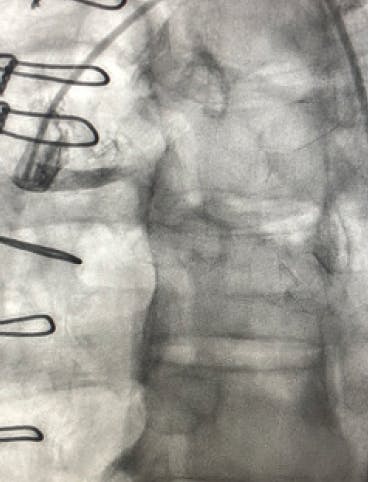

An Impella® device (Abiomed, Inc.) was placed emergently on arrival, and perfusion was restored. The initial angiogram showed an occlusion of the proximal left anterior descending (LAD) artery with an acute cutoff, consistent with thrombosis (Figure 1). The lesion was wired with a 0.014-inch balance middleweight wire (BMW; Abbott). CAT RX was used frontline, and flow was restored after two passes with 30 seconds of aspiration (Figure 2). The door-to-device time was 45 minutes. After mechanical thrombectomy, intravascular ultrasound was performed, revealing evidence of plaque rupture and minimal associated plaque burden. Primary stent implantation was therefore performed with a 3- X 28-mm DES, which was postdilated with a 3.25-mm noncompliant balloon to 18 atm. Final angiography revealed TIMI 3 flow with no evidence of distal embolization and restoration of myocardial blush (Figure 3). The Impella® device was removed at the end of the procedure. The patient experienced a full recovery and was discharged from the hospital after 3 days.

Figure 1. Initial angiogram showing occlusion of the proximal LAD.

Figure 2. Flow through LAD after mechanical thrombectomy with CAT RX.

Figure 3. Final angiogram showing TIMI 3 flow through the vessel.